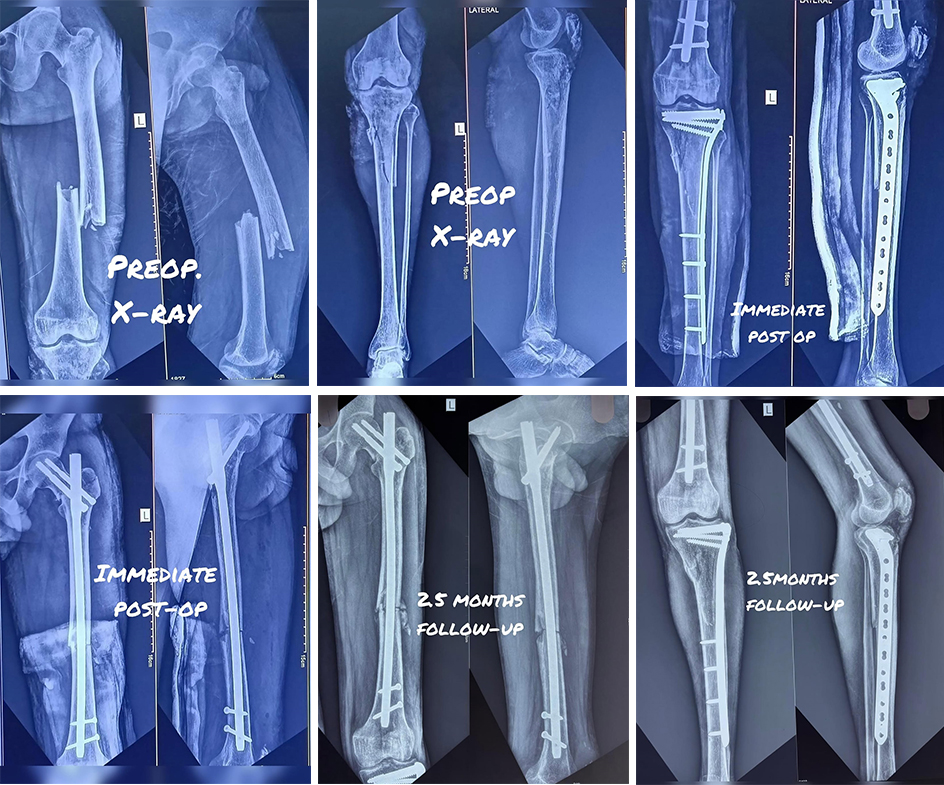

- This young patient suffered a severe injury to his left lower limb following a high-impact trauma. The X-rays show multiple complex fractures involving both the thigh bone (femur) and the leg bones (tibia and fibula) and knee cap.

- Luckily, was able to fix all in almost perfect alignment and here are the result after 2.5 months of surgery.

- Patient has regain almost full movement at knee with no extension lag and the nail was dynamized.